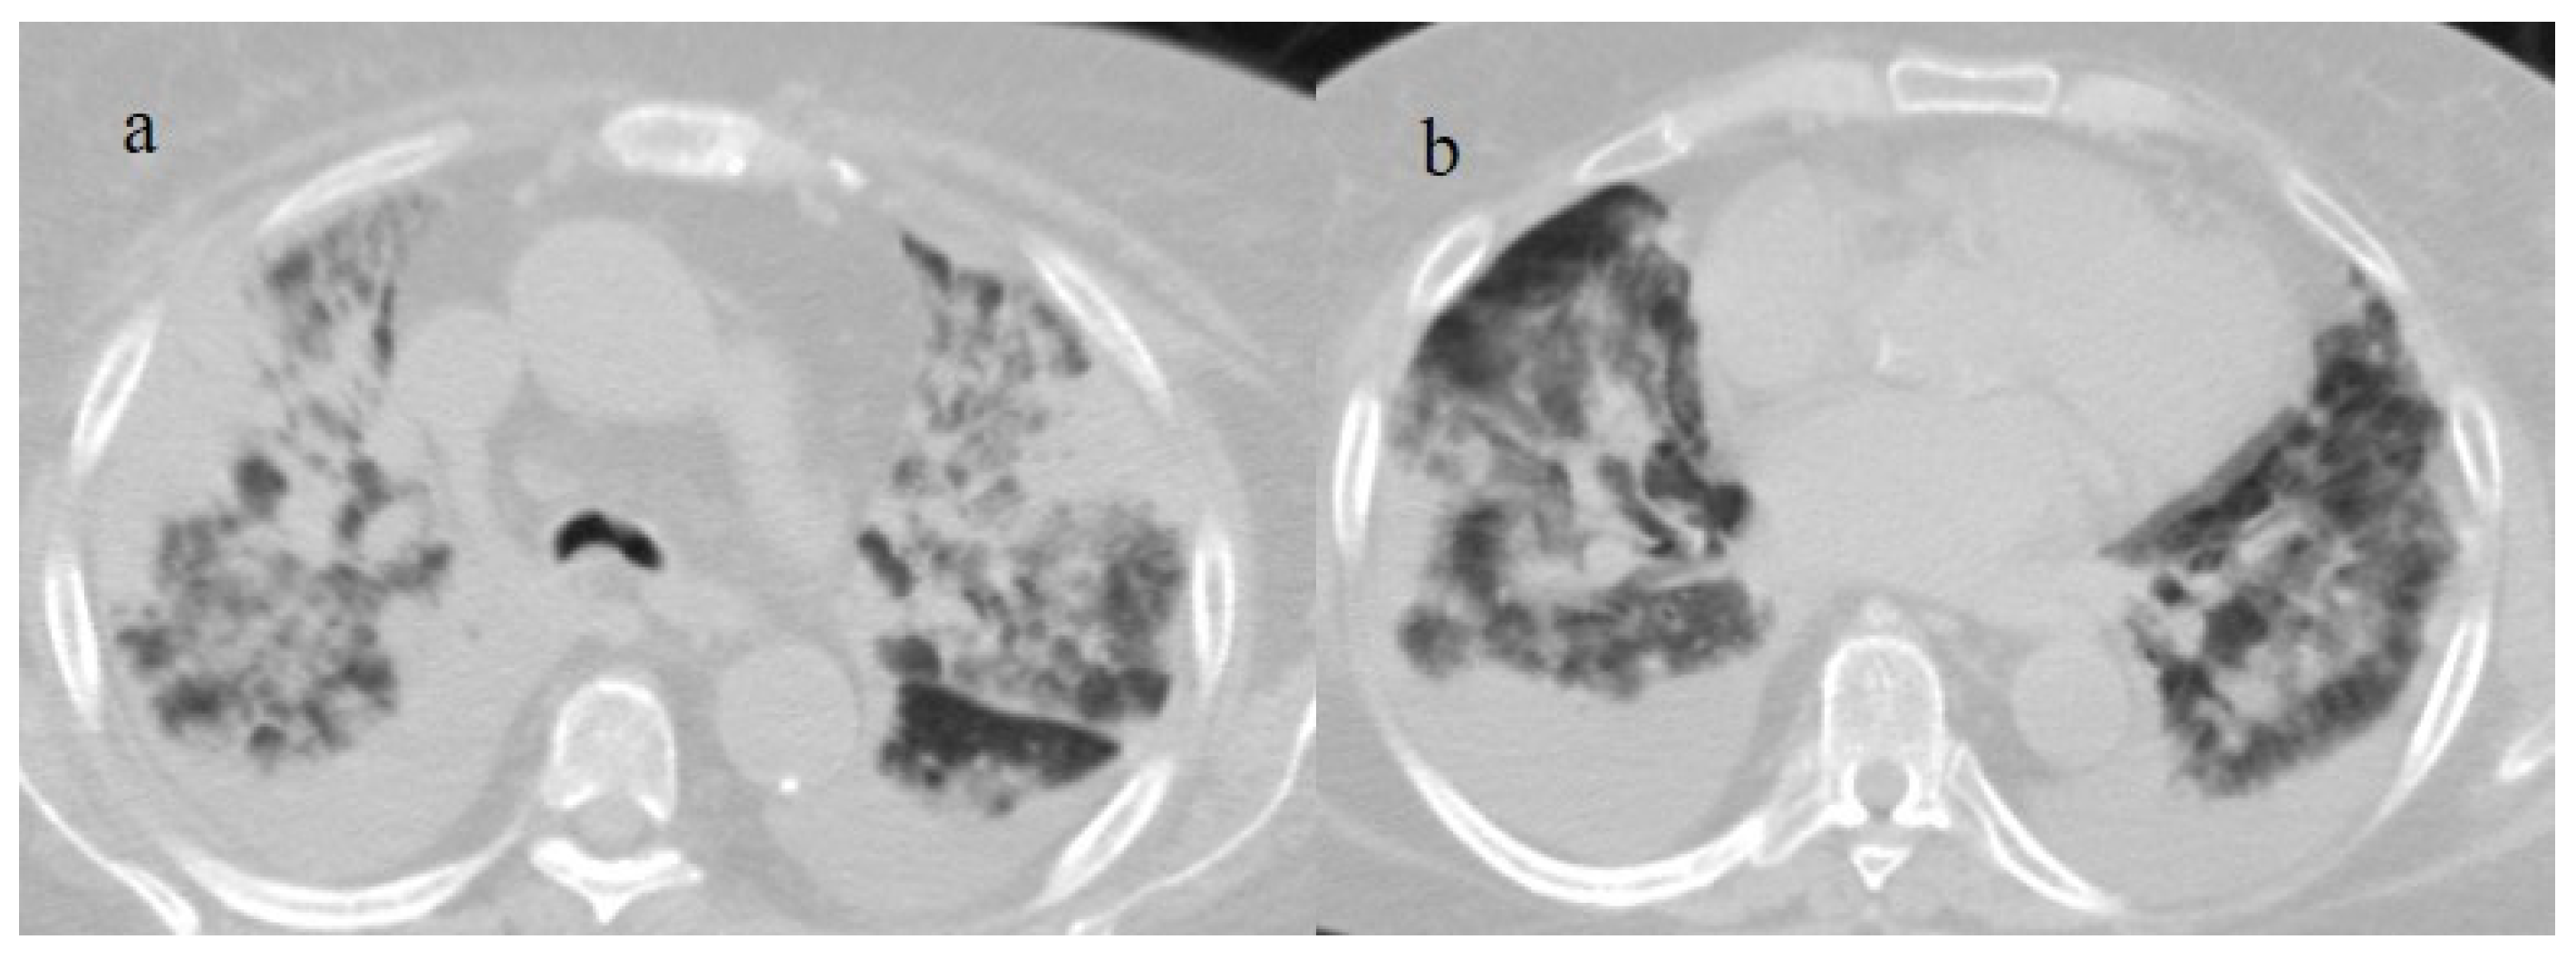

3.2. COVID-19 Pneumonia after Breakthrough Infections

3.3. Secondary Lung Complications